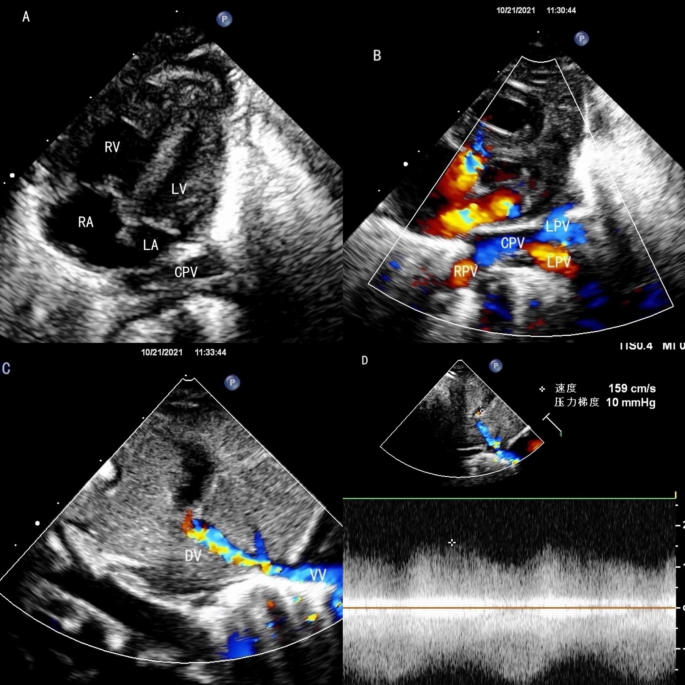

All 48 cases underwent echocardiographic examination to evaluate the pulmonary venous drainage pathways, the presence of obstruction, associated malformations, and cardiac function. Among the 15 supracardiac types, nine cases drained into the innominate vein and six into the superior vena cava (SVC) (Fig. 1). There were 13 single vertical vein and 2 cases of double vertical veins. In the 20 cardiac cases, 17 CPVs drained into the RA via the coronary sinus (CS) (Fig. 2), two CPV drained directly into the RA, and one had four pulmonary veins draining separately into the RA. Among the 10 infracardiac cases, eight cases had CPVs that drained into the portal vein via a vertical vein, one drained into the hepatic vein, and one drained into the inferior vena cava via ductus venous (Fig. 3). In the three cases mixed-type cases, all of them combines both supracardiac and cardiac types (Fig. 4).

The echocardiography of infracardiac TAPVC. (A) The left heart is small, the posterior wall of the LA is smooth, and the CPV is behind the LA. (B) The pulmonary veins drain into the CPV. (C) The vertical vein goes down then drains into duct vein, the color doppler shows turbulent flow at the drainage site. (D) A non-phasic flow was detected at the drainage site.